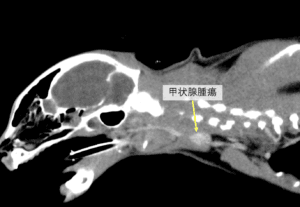

猫の甲状腺腫瘍

甲状腺は、首の気管の両側に位置し、体の代謝を調整する甲状腺ホルモンを分泌する臓器です。猫の甲状腺腫瘍はほとんど良性腫瘍(甲状腺腺腫)ですが、稀に悪性腫瘍(甲状腺癌)も認められます。猫では甲状腺ホルモンを過剰に分泌する機能 […]

犬の甲状腺腫瘍(甲状腺癌)

甲状腺は、首の気管の両側に位置し、体の代謝を調整する甲状腺ホルモンを分泌する臓器です。犬の甲状腺腫瘍は、全犬腫瘍の約1.2〜4.0%を占める比較的まれな腫瘍ですが、その63〜88%は悪性(甲状腺癌)とされています。発症年 […]